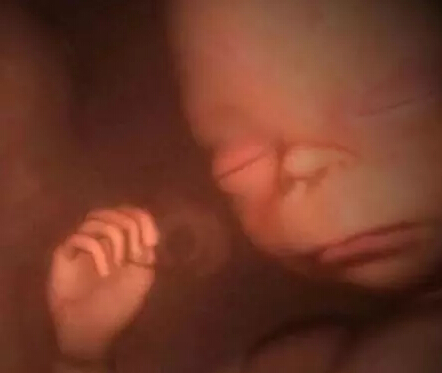

拥挤在子宫里的多胞胎

从4-D扫描图的特写镜头可以看到,这个差不多足月的胎儿在吸食羊水。这有助于胎儿为迎接子宫外的生活锻炼消化系统。

在这里你甚至可以清晰辨认出画面前方这个双胞胎胎儿手上的根血管。